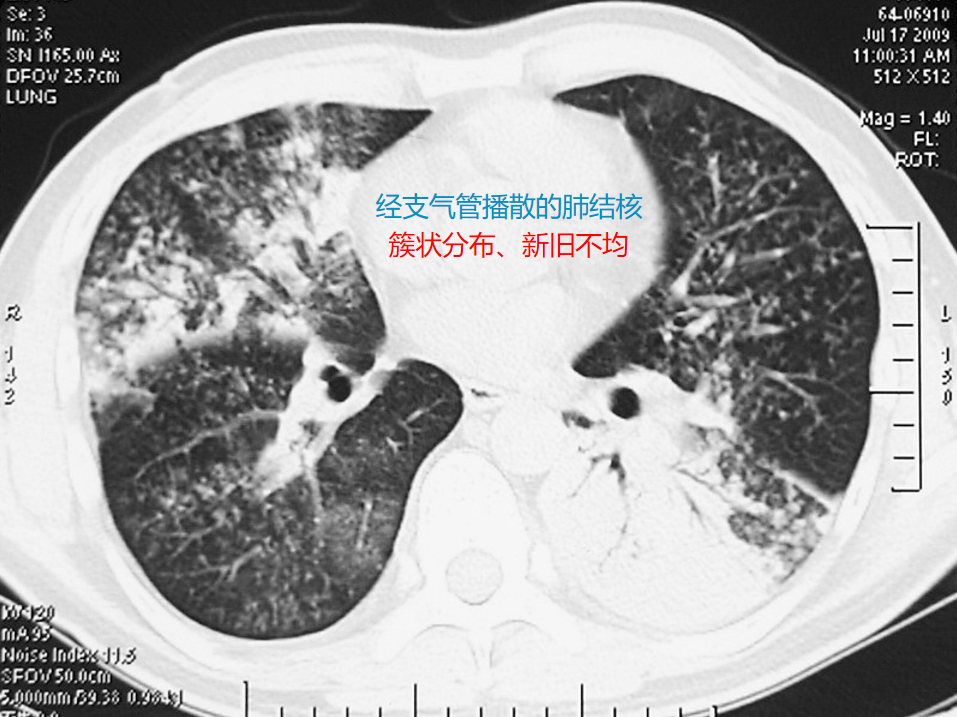

簇状分布的小叶中心性微结节、新旧不均,可伴树芽征或空洞。

这张CT显示的是经支气管播散的肺结核的典型表现:簇状分布的小叶中心性微结节、新旧不均: